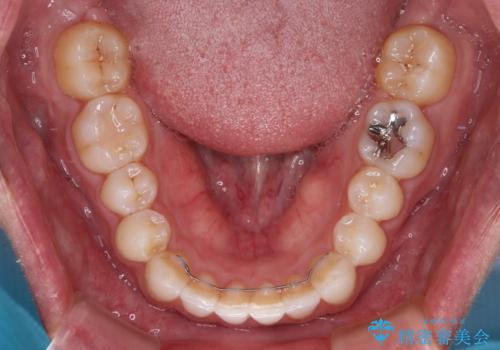

- 前歯のデコボコとクロスバイトを治したいとのことで来院された患者様です。

上下顎ともに歯列全体の側方拡大を行い、下顎前歯はIPR(歯と歯の間を削る)によってデコボコとクロスバイトが解消するように設計し、インビザラインにより治療を行うこととしました。

2年弱で終了する予定でしたが、途中来院されなかった時期があり、その後舌側転位している前歯を動かせるところまで動かしたいとのことで4年ほど治療を継続されました。